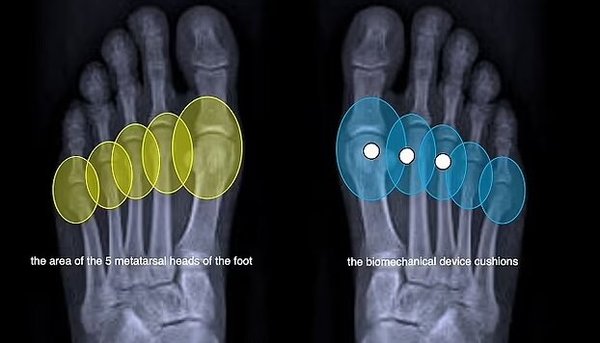

این کفی که توسط شرکت ایتالیایی «GAIT-TECH» ساخته شده است، ضربه را هنگام راه رفتن از بین میبرد و فشار را در سراسر پا پخش میکند. این کفی در دید نیست و به طور ناخوشایند زیر پا تکان نمیخورد.

به گفته این شرکت مستقر در کاپری، نوآوری بیومکانیکی این کفی که از پلیمر بازیافتی ساخته شده است، سلامتی زنان را بهبود میبخشد، درد را تسکین میدهد و از بروز آسیبها جلوگیری میکند.

کفشهای پاشنهبلند، تمام وزن کاربر را روی قسمت جلوی پا قرار میدهند و فشار شدیدی را بر انتهای استخوانهای کف پا و مفاصل بین انگشتان و پا وارد میکنند. این امر به افزایش خطر شکستگی استخوان، ضخیم شدن بافت اطراف عصب پا و سایر آسیبهای احتمالی منجر میشود.